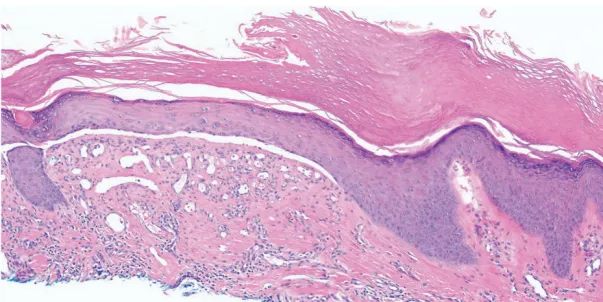

1.组织病理学检查(HE染色):显示局灶性苔藓样皮炎伴真皮-表皮交界处表皮下分离及真皮纤维化,未见空泡变性或嗜酸性粒细胞浸润。同时存在角化过度、棘层增厚和表皮萎缩区域(图B)。

图2 皮损组织病理学图像(HE染色,×10):篮网状角化过度,其下方表皮呈棘层增厚与萎缩相间,稀疏的淋巴细胞组织细胞围管性皮炎,伴表皮下分离及真皮纤维化。